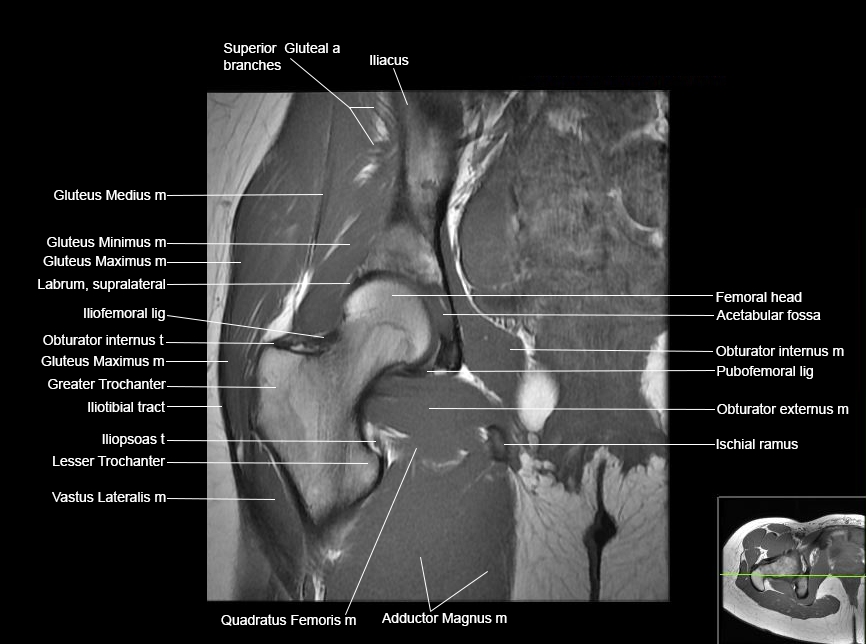

Hip

Basic Hip MRI

MRI Hip Anatomy

Scroll using the mouse wheel or the arrows